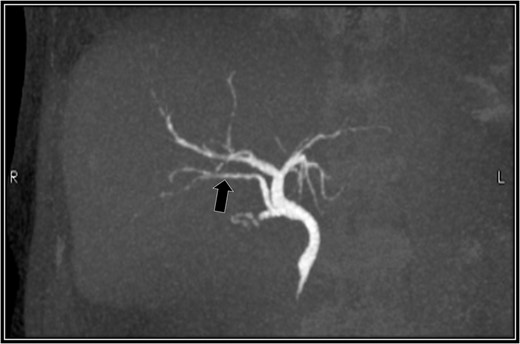

A 48-year-old Japanese man experienced abdominal pain after dinner. He underwent computed tomography (CT), and we observed stones in his cystic duct (Fig. 1). Hematological findings showed no liver dysfunction. A magnetic resonance cholangiopancreatography (MRCP) scan demonstrated that the right accessory hepatic duct branching from the cystic duct dominated an anterior segment of the right hepatic lobe (Fig. 2). Therefore, we diagnosed him as cholelithiasis with an anomalous biliary tract, and LC was planned.

Preoperative magnetic resonance cholangiopancreatography scan. The right accessory hepatic duct branching from the cystic duct (black arrow) dominates an anterior segment of the right hepatic lobe.